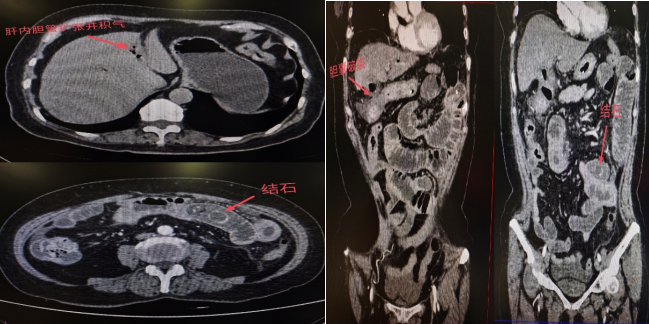

随后腹部CT检查结果显示:李阿姨的胆囊已经发生穿孔,一枚结石从破口处掉进小肠,并牢牢卡在肠腔内,形成了机械性肠梗阻。 更严重的是,由于结石嵌顿时间较长,已导致局部肠壁明显水肿、炎症。

12月16日,周亮主任为李阿姨施行了小肠切开取石术 。手术中,周亮主任在李阿姨的小肠内共取出三枚结石,最大的一枚直径约5厘米,类似于鸡蛋形状。